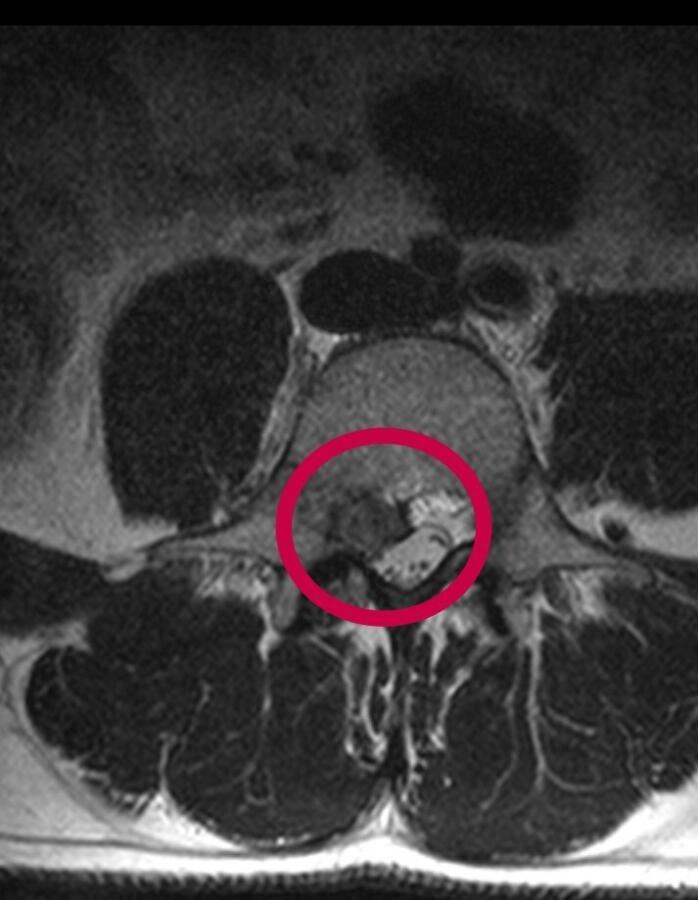

Düzce Üniversitesi Hastanesi’nin başarısı ülke sınırını aştı. 23 yıldır İskoçya’da yaşayan ve orada kuaför olan 40 yaşındaki Yasin Emre Meydan çektiği ağrılardan Düzce’de kurtuldu. Yaşadığı İskoçya’da rahatsızlığına bir türü çözüm bulamayınca tatil için geldiği memleketi Düzce’de, Düzce Üniversitesi Hastanesi’nde yapılan tetkikte bel fıtığı olduğu tanısı konuldu. Düzce Üniversitesi Tıp Fakültesi Hastanesi Beyin ve Sinir Cerrahisi Anabilim Dalı Doç. Dr. Cengiz Tuncer’in yaptığı başarılı ameliyat ile Yasin Emre Meydan sağlığına kavuştu.

Doç. Dr. Cengiz Tuncer de “İskoçya’dan bel fıtığı tanısı ile ameliyat olmak için Düzce’mize gelen hastamızın operasyonunu başarı ile tamamladık” dedi.